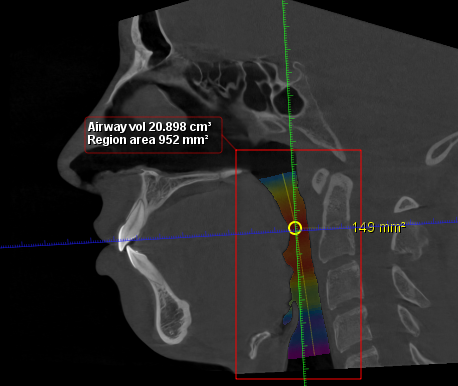

Double Jaw Surgery + Genioplasty

At least 4* of counter clockwise rotation on both jaws.

5mm+ advancement on both maxilla and mandible

7mm+ genioplasty

My jaw surgery movements are limited because of my natural unfortunate teeth position and a combination of other factors.

Double Jaw Surgery + Genioplasty

At least 4* of counter clockwise rotation on both jaws.

5mm+ advancement on both maxilla and mandible

7mm+ genioplasty

My jaw surgery movements are limited because of my natural unfortunate teeth position and a combination of other factors.